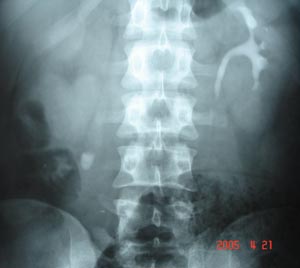

Intravenous Urography

It reveals a staghorn calculas on right side with absent nephrogram on right side. Left kidney shows compensatory hypertrophy.